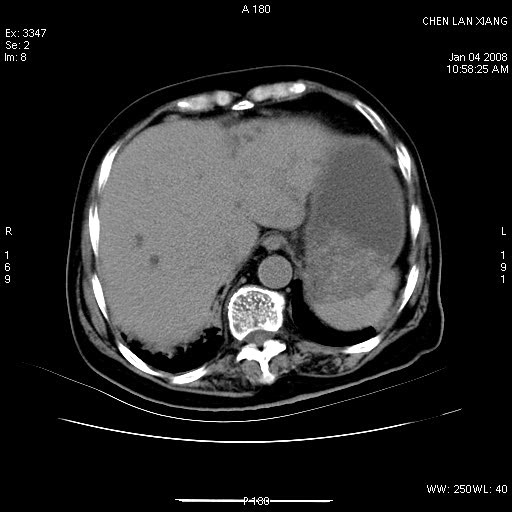

女,76岁,腹痛3-4天,b超示:肝内实性肿物,胆囊强回声,胆总管扩张.

1 胆总管末端结石伴肝内胆管结石,肝内外胆管扩张。2 胆囊扩大,胆囊壁不规则增厚,内见软组织密度影。考虑:慢性胆囊炎,不除外胆囊癌!

胆囊内结增强影,肝内胆管、胆总管扩张明显。肝内胆管、胆总管下段多发结石,胆囊癌,建议mrcp检查

肝内外胆管多发结石;胆囊癌;

胆总管及肝内胆管多发性结石并扩张。

1)胆囊癌伴肝脏转移。2)胆总管下端结石、肝内胆管结石伴肝内外胆管扩张。